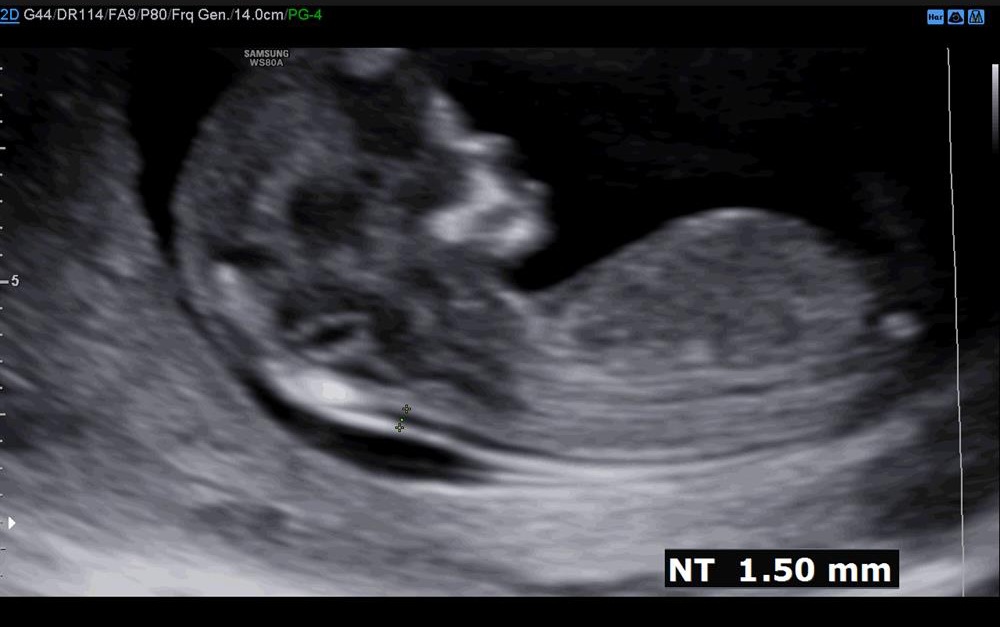

سونو ان تی😊😊😊😊😘❤

سلام ببخشید این تاپیک مال خیلی وقت پیشه شما هنوزم تو سایت هستید منم عکس سونو ان تی بذارم برای زحمت بیافتین منم حدس بزنید جنسیتو؟